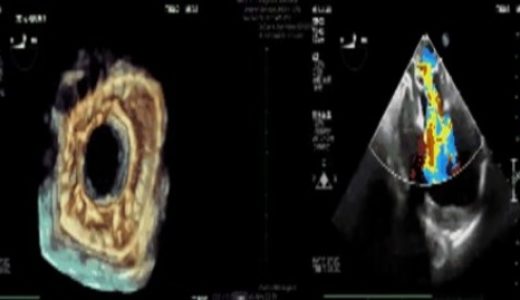

至鑫医疗完成介入二尖瓣置换产品动物实验

(医药健闻2022年3月3日讯)日前,至鑫医疗在泰州美凤力动物实验中心顺利完成了其自主研发的介入二尖瓣置换产品动物实验,…